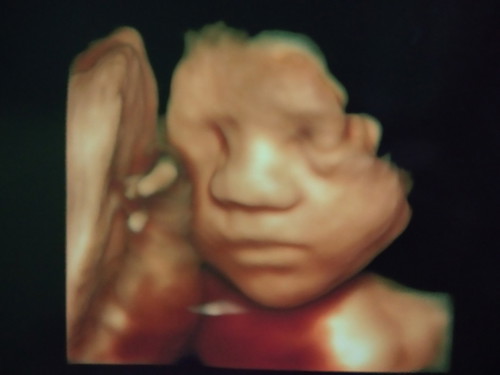

Abis nengokin dedek bayi alhamdulillah dapet dedek cewek lagi dan insyaallah HPL nya 24 Desember.. Adakah disini bunda bunda yg HPL nya sama dengan ku dan persiapan apa aja yg udh dibeli nih bunda??